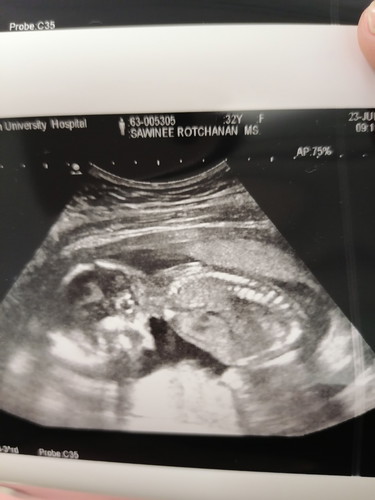

คุณหมอนัดวันนี้ ซาวด์ให้ดูน้องนอนคว่ำอีกแล้วค่ะ เดือนที่แล้วก็นอนคว่ำ17สัปดาห์ค่ะ แม่บ้านไหนลูกนอนคว่ำแบบนี้บ้างคะ นอนคว่ำบ่อยๆนี่ปกติไหมคะ